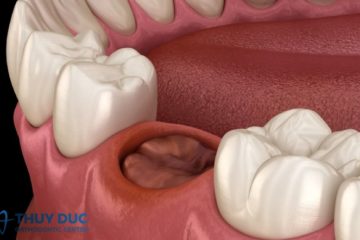

Khi nào nên nhổ răng sữa cho trẻ?

Quá trình thay răng sữa để nhường chỗ cho răng vĩnh viễn là một cột mốc quan trọng trong sự phát triển của trẻ. Tuy nhiên, không phải lúc nào răng sữa …